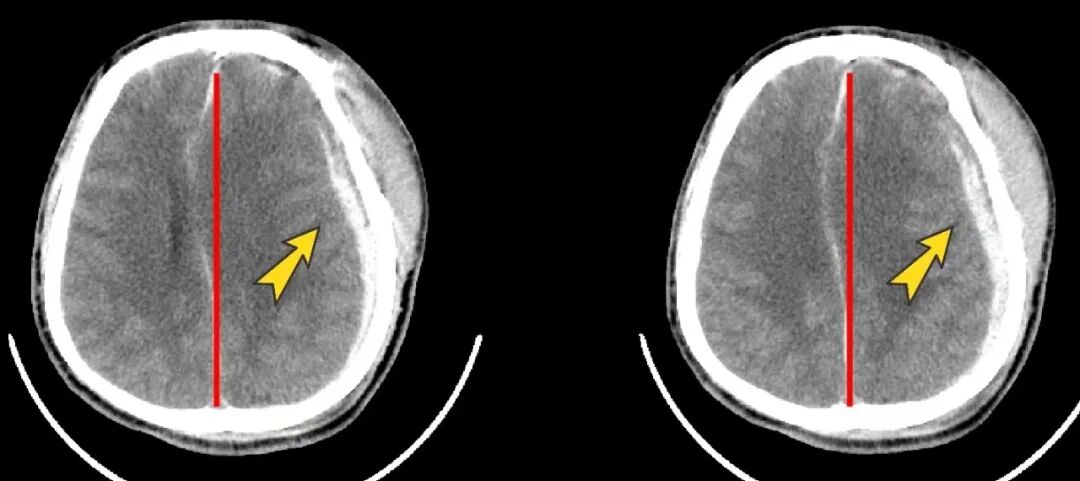

患者病情越來越重,意識(shí)逐漸變差,惠州三院神經(jīng)外科團(tuán)隊(duì)及時(shí)為其行神經(jīng)內(nèi)鏡下“硬膜下血腫清除術(shù)”。在醫(yī)護(hù)團(tuán)隊(duì)的精心治療和護(hù)理下,吳伯最終順利康復(fù)出院!

患者術(shù)后CT